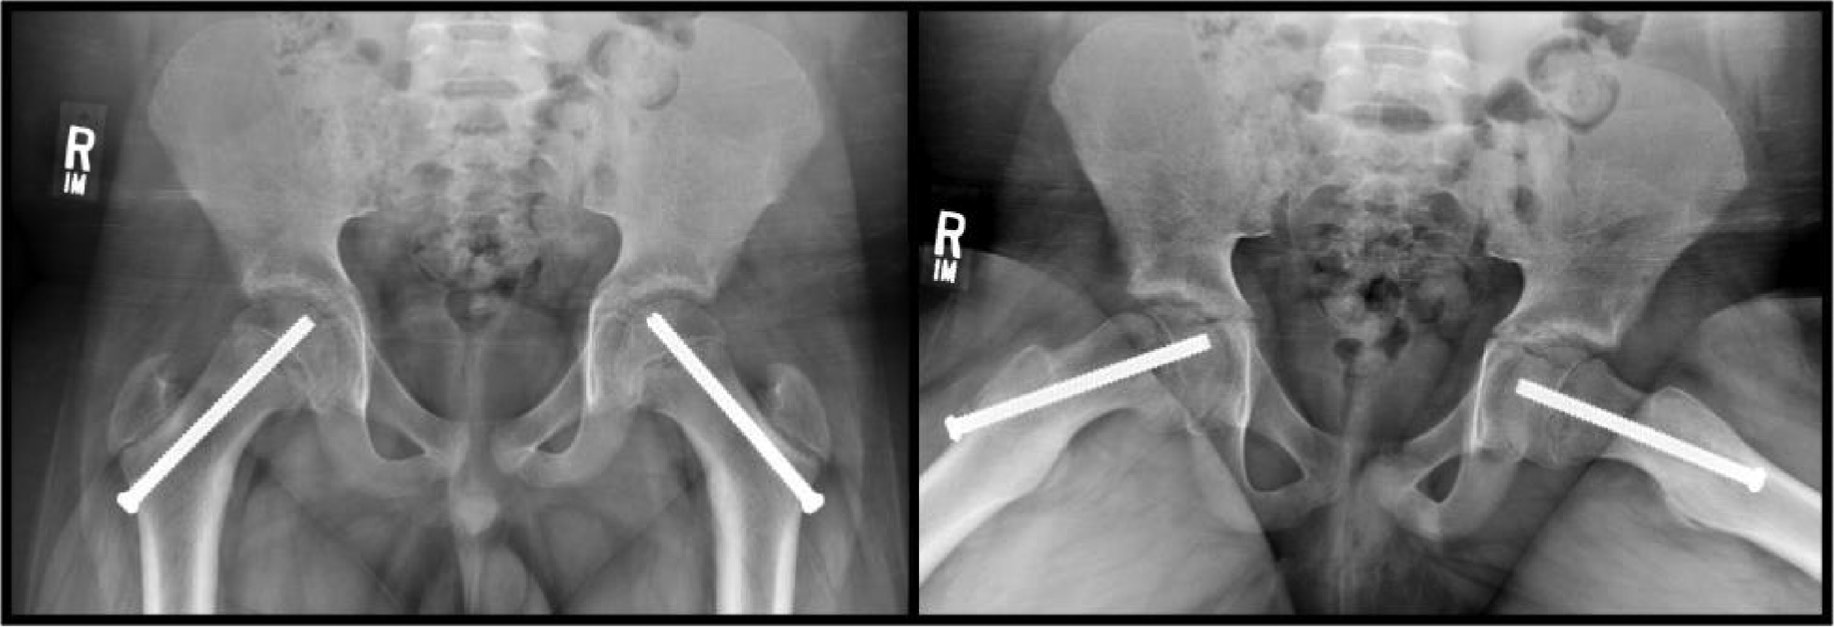

In an attempt to further reduce rates of osteonecrosis associated with unstable SCFE, Schrader et al.57 described a technique for intraoperative monitoring of epiphyseal perfusion. An intracranial pressure (ICP) probe was inserted percutaneously through a cannulated screw into the epiphysis. The presence of a pulsatile waveform synchronous with cardiac monitoring suggests that perfusion to the epiphysis is maintained. This technique provides not only prognostic value but may also help confirm the adequacy of the capsulotomy performed after fixation of an unstable SCFE (Figure 5).

Figure 5. In cases of unstable SCFE, a capsulotomy is performed (such as with a Cobb elevator) to decompress intracapsular hematoma, which could otherwise lead to tamponade and decreased epiphyseal perfusion. (A) An intracranial pressure sensor can be threaded through the cannulated screw in the epiphysis. (B) Sensor seen extending beyond the tip of the inferior screw to assess for femoral head perfusion. A pressure waveform (C, orange) from the intracranial pressure sensor that is synchronous with the cardiac monitoring (C, green waveform) is prognostic of maintained epiphyseal perfusion.

jposna2022589_fig5.jpg